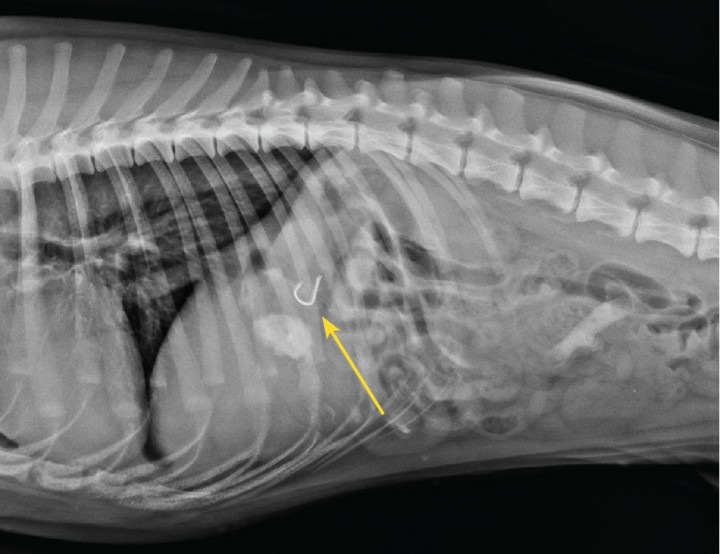

Por temas económicos, los propietarios solo autorizaron la repetición de una proyección radiográfica con el fin de observar un posible desplazamiento en sentido aboral del cuerpo extraño (Fig. 1), Para ello se sedó al animal con una combinación de medetomidina 0,01 mg/kg i.m. (Sedin® 1 mg/ml; Laboratorios Calier; Les Franqueses del Vallès), ketamina 1 mg/kg i.m. (Imalgene® 100 mg/ml; Laboratorios Merial; Sant Cugat del Vallès) y butorfanol 0,1 mg/kg i.m. (Butomidor® 10 mg/ml; Laboratorios Richterpharma AG; Wels). Una vez confirmada la ubicación del anzuelo en el estómago, se procedió a realizar la endoscopia bajo anestesia general. La inducción se realizó con propofol 1-4 mg/kg i.v. (Propofol Lipuro® 10 mg/ml; Laboratorios Braun; Rubí) y el mantenimiento anestésico con isofluorano al 1,5 % por vía inhalatoria (IsoVet® 1000 mg/g; Laboratorios Braun; Rubí).

<p>Radiografía laterolateral derecha. Se aprecia el anzuelo (flecha amarilla) localizado en el estómago. Es imprescindible la realización de una radiografía previa a la extracción endoscópica de un cuerpo extraño. En muchas ocasiones los objetos pueden cambiar de localización, desplazándose al intestino y, por tanto, fuera del alcance del endoscopio.</p>

Figura 1

Radiografía laterolateral derecha. Se aprecia el anzuelo (flecha amarilla) localizado en el estómago. Es imprescindible la realización de una radiografía previa a la extracción endoscópica de un cuerpo extraño. En muchas ocasiones los objetos pueden cambiar de localización, desplazándose al intestino y, por tanto, fuera del alcance del endoscopio.